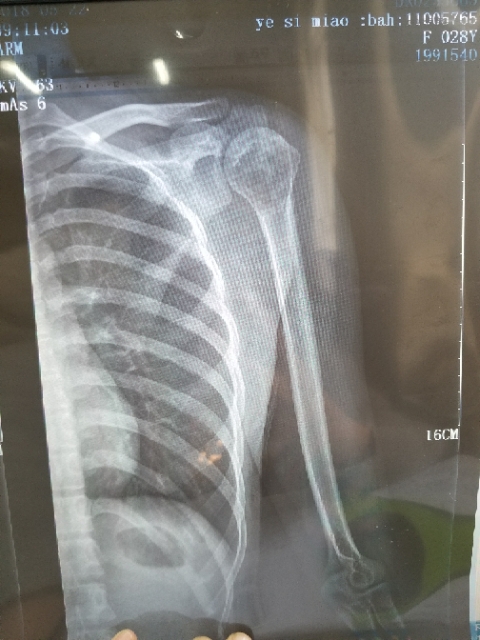

身心俱疲斗争 02019-02-22 患者家属女儿14岁,明天做截肢手术。医生让从髋关节处截,想保留个七八公分。问问大神们髋关节以下留七八公分能用常规的假肢吗? ...